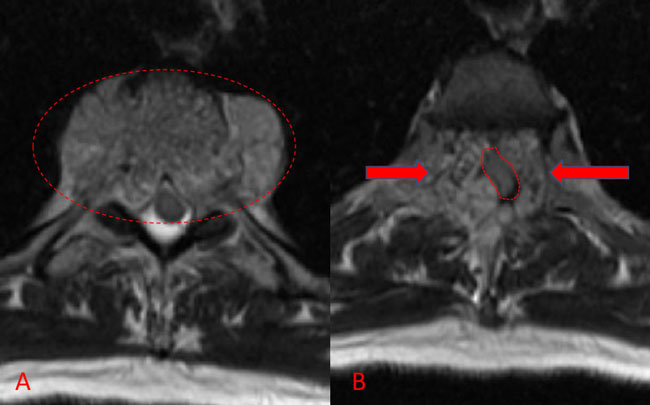

Figure 1. A) Sagittal T2 MRI demonstrates aggressive hyperintense T3 hemangioma involving the body and posterior elements compressing the thoracic spinal cord (arrows)

Figure 1. B and C) Axial MRI images of T3 demonstrates extensive infiltrative lesion with extradural compression of the thoracic spinal cord. (Dashed lines in A) tumor infiltration; Dashed lines and Arrows in B) cord compression.

He presented to the emergency room with one-week history of thoracic pain in addition to bilateral lower extremity weakness and paraparesis. MRI imaging with contrast showed a diffuse abnormal signal within the vertebral body of T3 and the posterior elements with lobulated soft tissue lesion extension into both paraspinal areas (Figure 1. A, B, C).